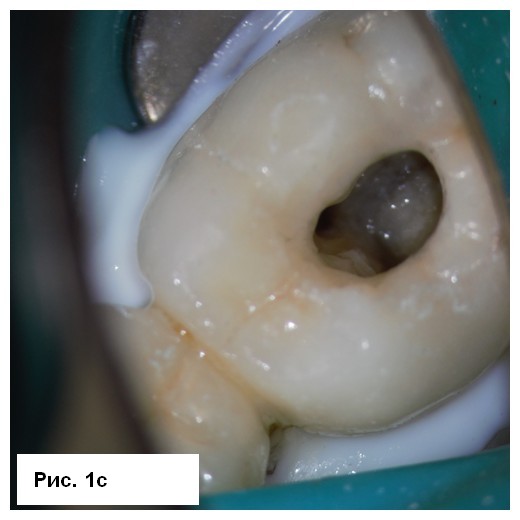

На рентгенограмме (рис. 1а) отмечались большие радиолюсцентые очаги на обоих корнях. Был поставлен диагноз: «некроз пульпы и острый апикальный абсцесс зуба 46». После консультации со стоматологом-ортопедом было принято решение провести эндодонтическое лечение с доступом к корневым каналам через существующую коронку. После вскрытия полости зуба было получено большое количество гнойного отделяемого с кровью (рис. 1b). Дренажу благоприятствовала ирригация 3 % NaOCl (рис. 1с), проведена инструментация корневых каналов системой 2Shape (MICRO-MEGA) и определена рабочая длина (рис. 2.а). Корневые каналы были заполнены гидроксидом кальция.